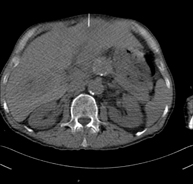

- TC Abdomen

Prueba diagnóstica que consiste en obtener imágenes del abdomen de alta definición anatómica (hígado, vesícula biliar, vía biliar, páncreas, bazo, estómago, intestinos, riñones, estructuras vasculares, vejiga, útero y ovarios, etc.) mediante el empleo de un equipo de TC (Tomografía Computarizada). Dichas imágenes se estudian posteriormente en una estación de trabajo que permite reconstrucciones bidimensionales en diferentes planos del espacio, y también reconstrucciones 3D (volumétricas). La mayoría de estudios requieren el empleo de contraste yodado para mejorar la definición de las imágenes.